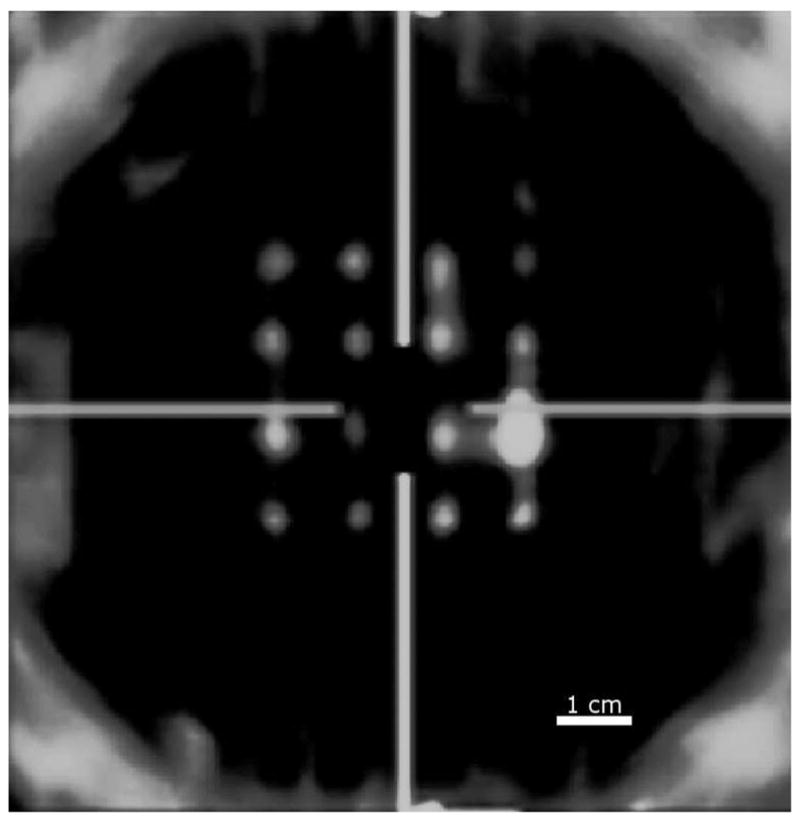

Fig. 3.

The figure shows a screen shot of the C-mode image at the depth of the pins. The image demonstrates the qualitative calibration of the translation stage before any phantom data were acquired. The horizontal lines shows the lateral orientation of the transducer, and the vertical lines show the elevational orientation of the transducer.